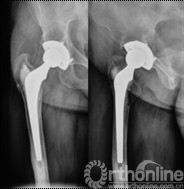

女,50岁,因髋关节发育不良继发骨关节炎行混合性固定(非骨水泥髋臼,骨水泥柄)THA手术。术后6年4个月发现腹股沟部渐增大、无痛性包块;体查:关节活动正常,腹股沟处可触及一10mm×10mm大小、质中等、移动度差、无触痛包块。超声检查提示右髂窝包块,呈强弱不等回声,大小约12cm×10cm,边界清楚。Harris评分88分。X线片示髋臼顶部DeLee和Charnley II区不规则低密度透光区,无连续骨小梁(图5)。CT片示髋臼假体上方DeLee和Charnley II区骨溶解区,DeLee和Charnley I、III区髋臼假体骨长入固定(图6)。WBC6.7×109/L,中性64%,ESR 28mm/h,CRP 8.34mg/L。聚乙烯线性磨损率为0.17mm/年,容积磨损率为543.42mm3/年,骨溶解区面积为412.52mm2。诊断:THA术后髋臼假体周围局灶性骨溶解(假体稳定)伴假性瘤样形成。

图5   翻修术前髋关节正侧位X线片示髋臼顶部DeLee和Charnley II区不规则低密度透光区(箭头所示),髋臼假体稳定固定

图9 髂腹股沟入路炎性假瘤切除、骨溶解病灶清除、同种异体颗粒骨植骨,髋关节后外侧入路更换高分子聚乙烯内衬为高交联聚乙烯内衬、更换股骨头术后

图10 术后2年随访,植骨替代吸收,髋臼骨溶解区新生骨组织替代,髋臼假体无移位、假体稳定固定